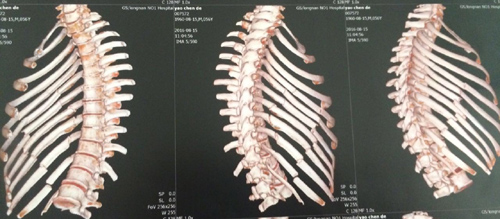

胸外科开展一例肋骨骨折切开复位内固定术

近日,胸外科对一例多发性肋骨骨折的病人进行了肋骨骨折切开复位+环抱器内固定术。手术过程顺利,患者术后恢复良好。

术前CT